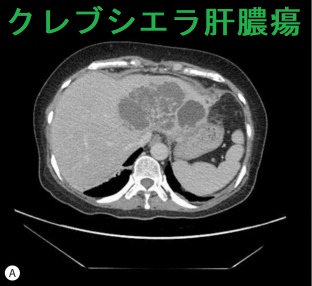

CIKPLA症候群(cryptogenic invasive K. pneumoniae-associated liver abscess)

CIKPLA症候群(cryptogenic invasive K. pneumoniae-associated liver abscess)は、主に東南アジアの糖尿病患者に発生するクレブシエラ菌(Klebsiella pneumoniae)肝膿瘍で、クレブシエラ肺炎から始まります。[Int J Infect Dis. 2007 Jan;11(1):16-22.]

クレブシエラ菌のクレブシエラ・ニューモニエ(Klebsiella pneumoniae、肺炎桿菌)はグラム陰性桿菌で、急性化膿性甲状腺炎と甲状腺膿瘍の起因菌。[Endocrinol Diabetes Metab Case Rep. 2020 Nov 26;2020:EDM200137.][J Diabetes Investig. 2016 Jan;7(1):127-9.]